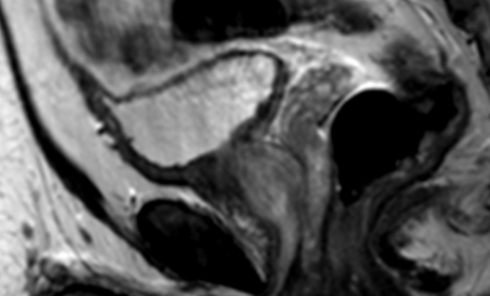

- L’ouraque relie le dome de la vessie à l’ombilic

- Il se ferme à la naissance donne le ligament ombilical

Kyste de l’Ouraque

- Deuxième plus fréquent (30%)